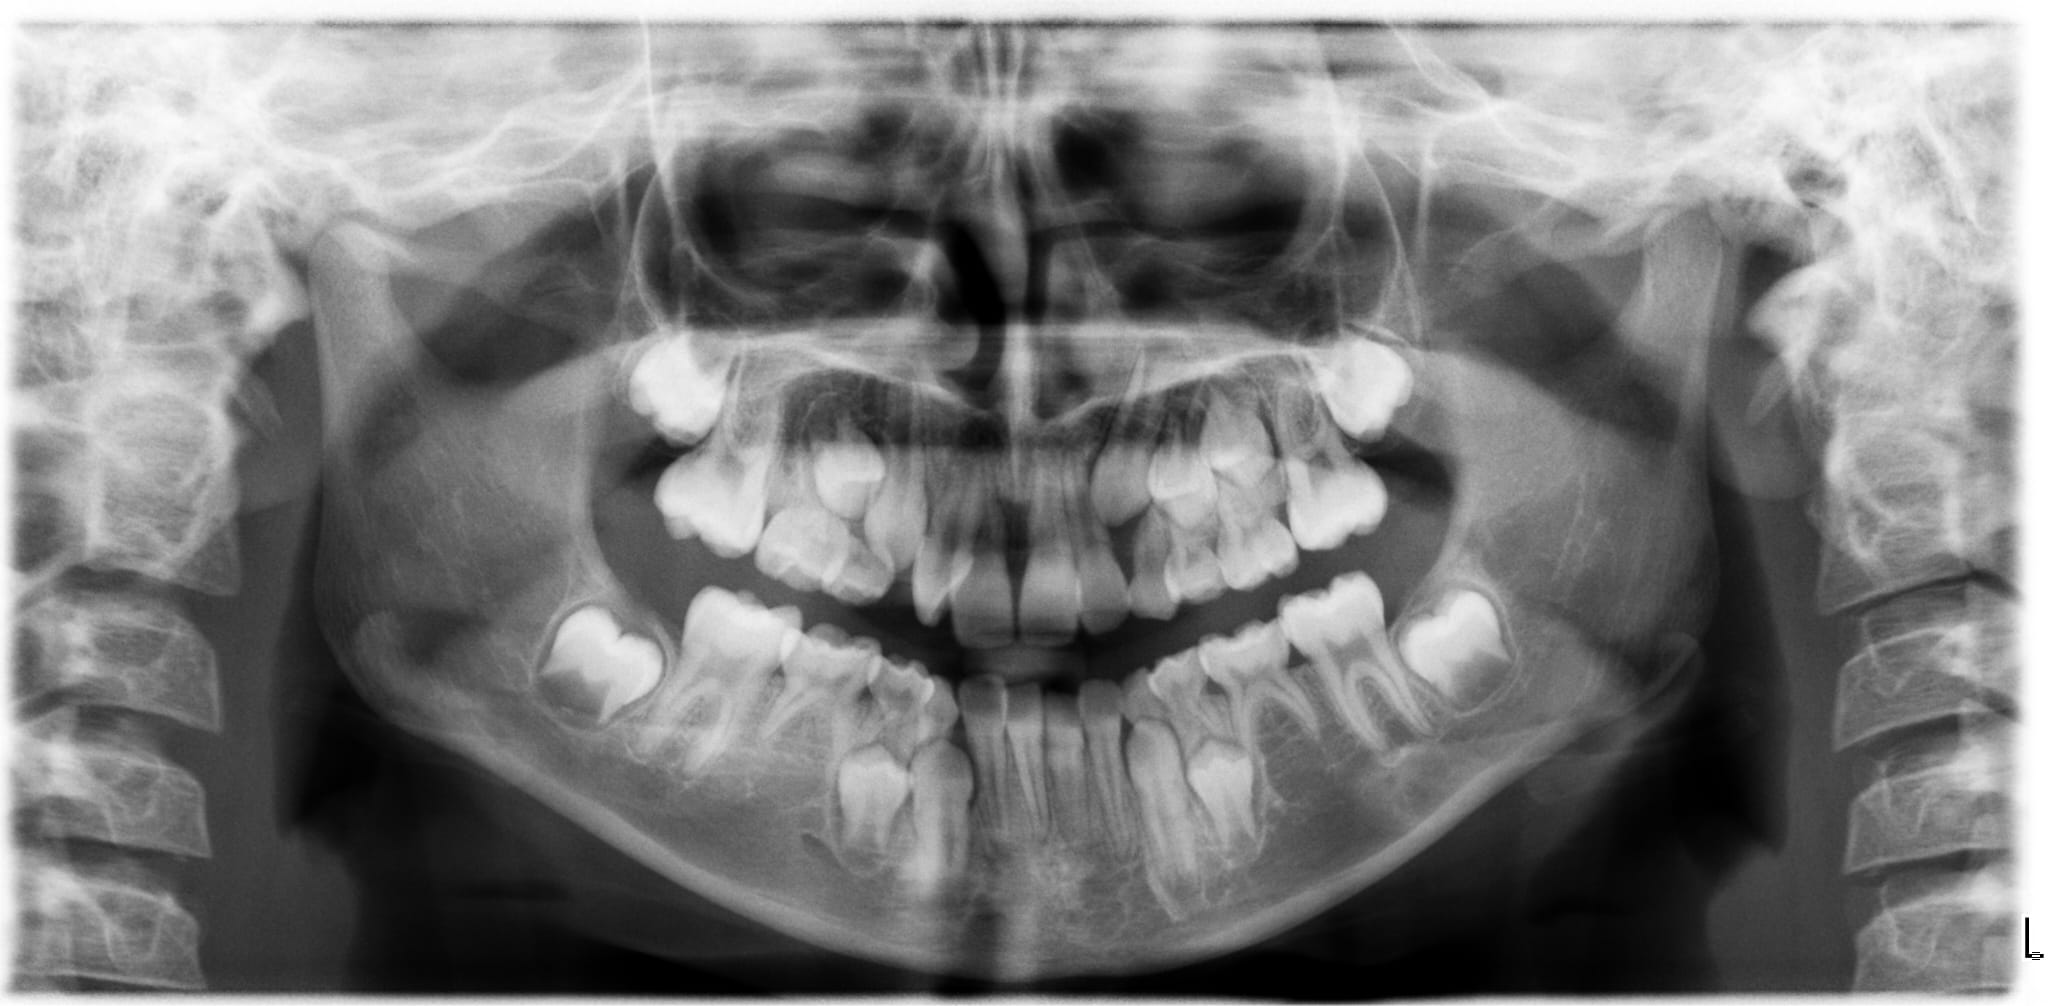

Afgelopen week heeft de tandarts een overzichtsfoto van het gebit van mijn dochter gemaakt (bijna 10).

N.a.v. deze foto heeft zij geconstateerd dat ze 2 kiezen en 1 tand zou missen. Maar als ik zelf naar de foto kijk dan lijkt het alsof ze meer kiezen mist (ze heeft nog geen kiezen gewisseld).